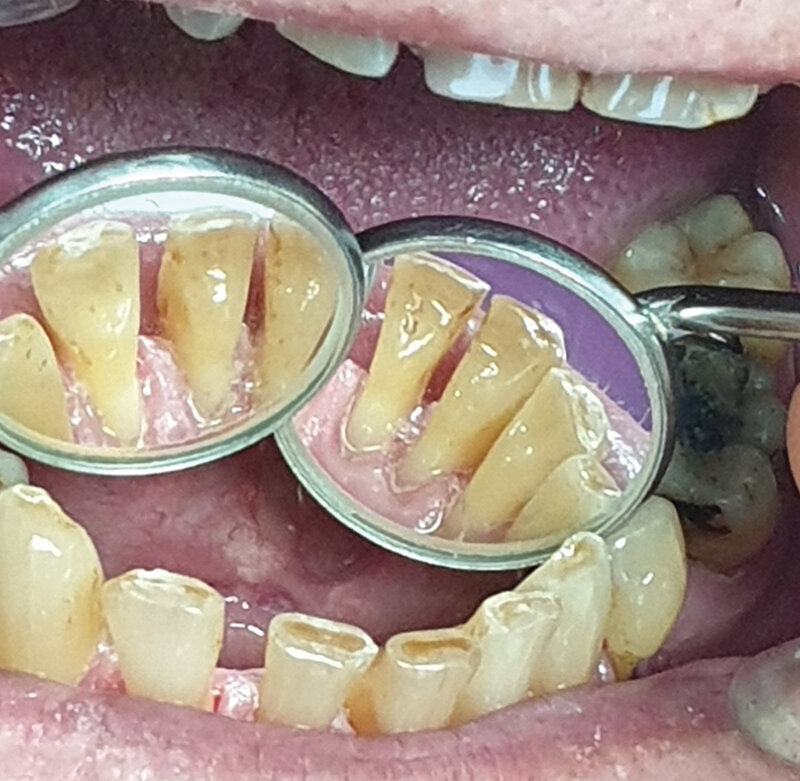

Pacijent B pušač pri prijemu. Estetski neprihvatljive pušačke pigmentacije na svim površinama zuba, naročito onim u estetskoj zoni, direktno izloženim glavnoj struji duvanskog dima. Zubni kamenac i meke naslage ukazuju na nizak nivo oralne higijene. Uočava se i prebojenost kompozitnih aproksimalnih plombi gornjih prednjih zuba. Slabije izražene melanogene pigmentacije desni. Jezik pacijenta takođe je obložen (Sl. 2.0).

Sl. 2.0: Pacijent B, pušač pri prijemu